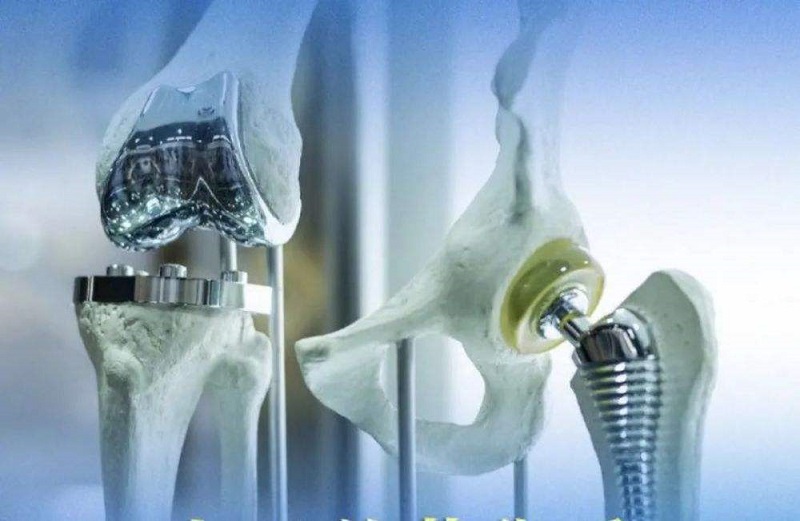

關(guān)節(jié)類植入物產(chǎn)品主要指實現(xiàn)因關(guān)節(jié)周圍骨折、累計關(guān)節(jié)的骨腫瘤及其他原因引起的骨缺損等關(guān)節(jié)障礙的關(guān)節(jié)功能重建的人體植入物,主要產(chǎn)品可分為人工膝關(guān)節(jié)、髖關(guān)節(jié)和肩關(guān)節(jié)以及小關(guān)節(jié)等。